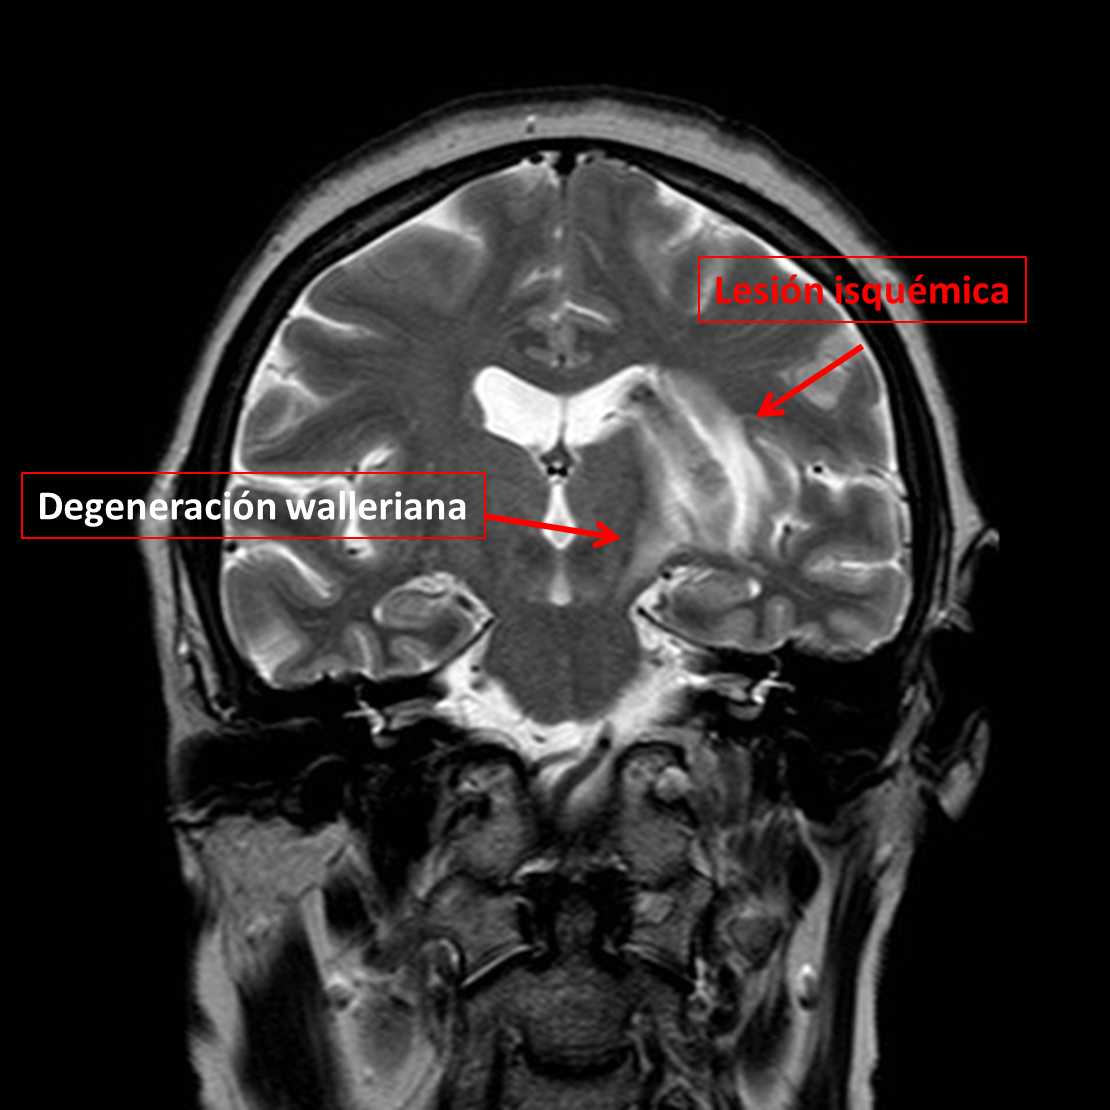

Se observa una lesión isquémica con una degeneración walleriana secundaria que también se observa en las secuencias de difusión y en el mapa ADC:

El motivo de presentar este caso es la presencia de una degeneración walleriana precoz que se observa en secuencias T2 coronal y la implicación pronóstica de este hallazgo.

De una forma sencilla, la evolución de las alteraciones en la señal de la resonancia cerebral a lo largo del tracto de sustancia blanca refleja los cambios bioquímicos que ocurren durante la DW. Las alteraciones en la difusión que se muestra hiperintenso y la hipointensidad de señal en el mapa ADC sí que se han descrito en la fase aguda en la primera semana distal a una lesión por encima y son indicativas de degeneración walleriana. Serían los cambios más precoces detectables. Las alteraciones de la DW de las secuencias T2 suelen aparecer en la 3-4 semana aunque hay casos muy precoces que aparecen en las 2ª semana. Este caso es particular por el hecho que aparece precozmente.